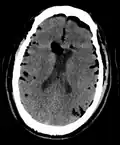

Pneumocephalus is the presence of air or gas within the cranial cavity. It is usually associated with disruption of the skull: after head and facial trauma, tumors of the skull base, after neurosurgery or otorhinolaryngology, and rarely, spontaneously. Pneumocephalus can occur in scuba diving, but is very rare in this context.

If there is a valve mechanism which allows air to enter the skull but prevents it from escaping, a tension pneumocephalus can occur (similar to what can happen in a tension pneumothorax).

CT scans of patients with a tension pneumocephalus typically show air that compresses the frontal lobes of the brain, which results in a tented appearance of the brain in the skull known as the Mount Fuji sign.[1][2][3] The name is derived from the resemblance of the brain to Mount Fuji in Japan, a volcano known for its symmetrical cone. In typical cases, there is a symmetrical depression near the midline (such as the crater of a volcano), due to intact bridging veins.[3] Its occurrence seems to be limited to tension pneumocephalus (not occurring in pneumocephalus without tension).[4] The sign was first described by a team of Japanese neurosurgeons.[5]